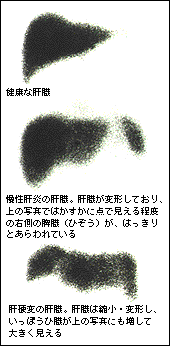

肝シンチグラフィーは、放射性のテクネシウムを使う方法で、肝臓の形を画面に映し、形や大きさの変化をとらえます。